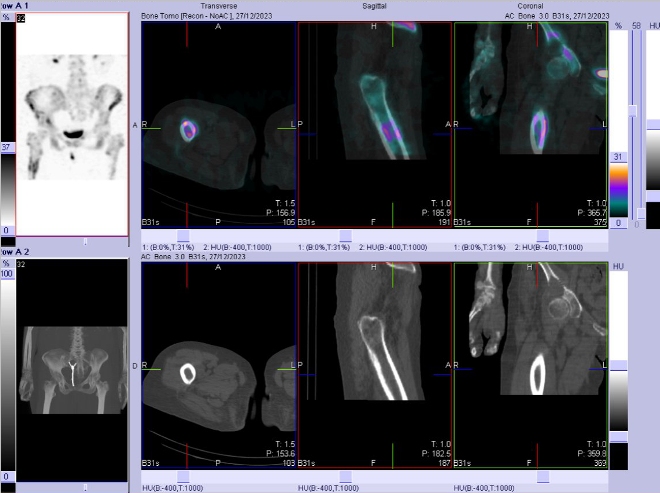

/ Obr. č. 8-10: Fúze obrazů SPECT a CT bederní páteře, pánve, kyčelních kloubů, proximální části stehenních kostí.

Patologické ložisko vyšší osteoblastické aktivity v proximální části diafýzy pravé stehenní kosti. Osteolytická léze v kosti kyčelní vpravo těsně nad pravým kyčelním kloubem zasahující zčásti i do acetabula, na jejím mediálním okraji je vyšší osteoblastická aktivita.

Nález odpovídá metastatickému postižení skeletu (jak osteolytická, tak osteoblastická metastáza). Degenerativní změny páteře.